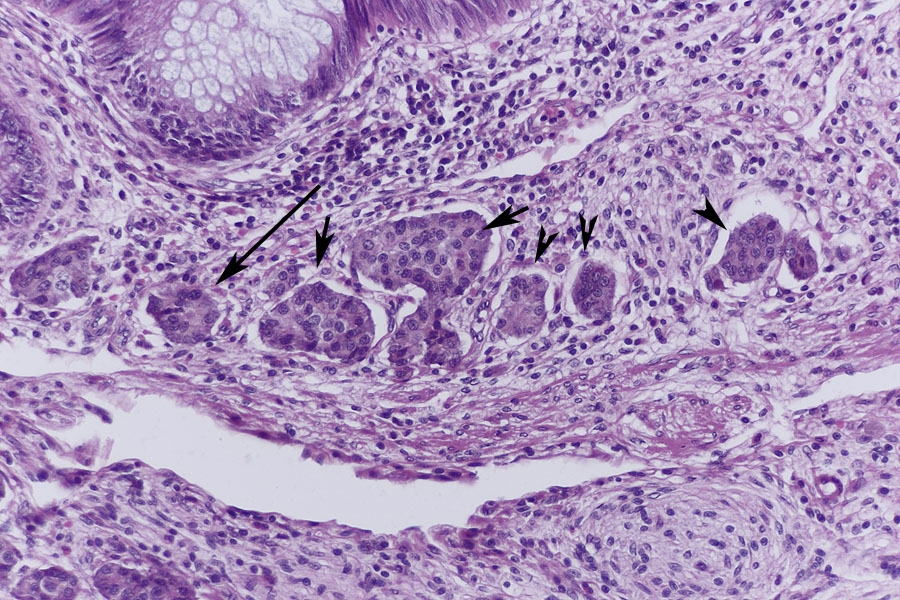

In der Submucosa fallen dann Inseln aus Zellen mit hellem Zytopasma auf (Pfeile) die ich

für Carcinoidzellen halte.

In der stärkeren Vergrößerung finden sich dann zahlreiche Carcinoidzellen, die aber auf die Submucosa beschränkt bleiben.